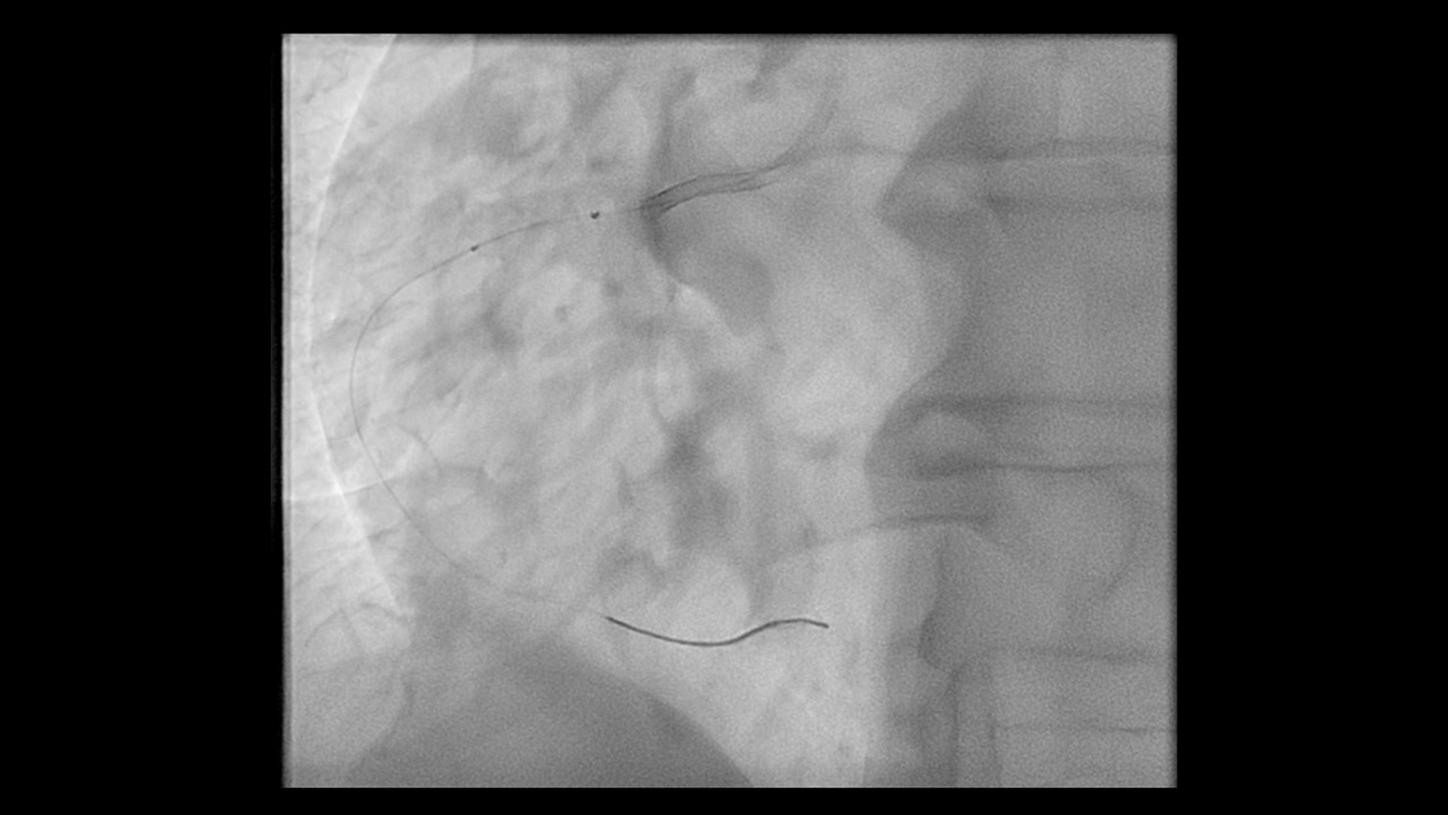

During minimally invasive procedures, it is critical to have a clear view of anatomies and devices. Yet complex imaging tasks or challenging patient conditions often impact image quality. OPTIQ AI delivers constant image quality1 defined by CNR in support of the ALARA principle, independent of patient or C-arm angulation. On top, an AI-powered algorithm reduces image noise in real time across different 2D imaging modes.

Make AI-powered imaging and clear insights your standard during interventions – with OPTIQ AI.